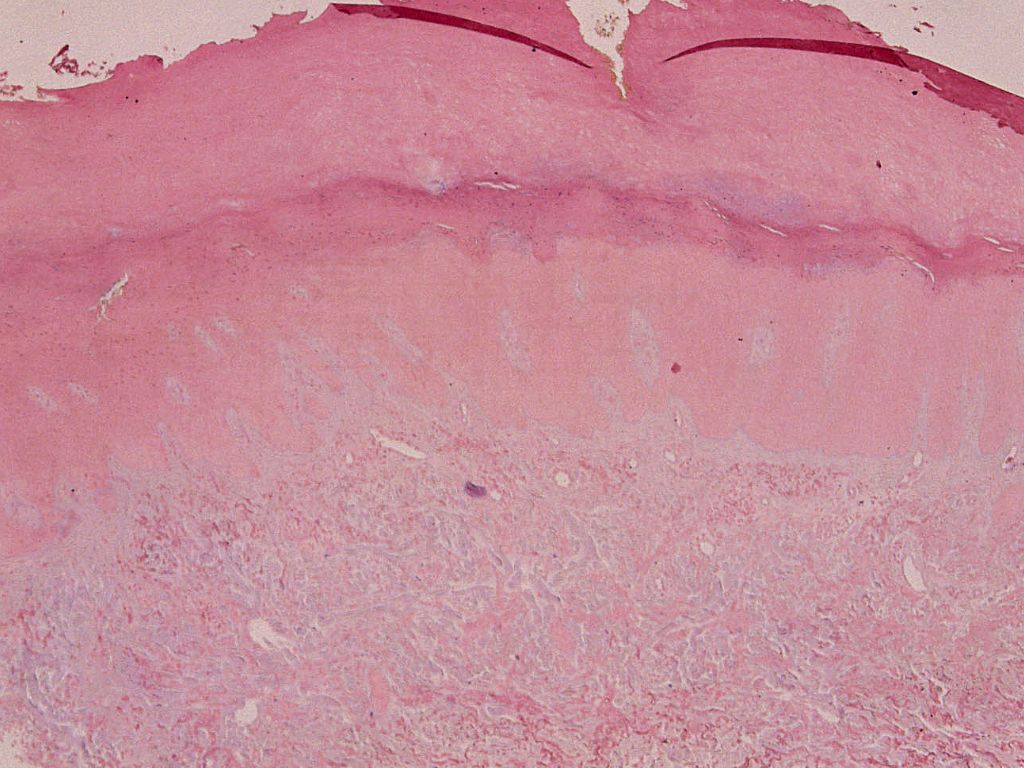

Diagnostiek:Biopt, speciaal vragen om mucine kleuring

en de DD vermelden. De patholoog kan bij mucine deposities aanvullend onderzoek

doen naar de herkomst er van (keratine, immunoglobuline).